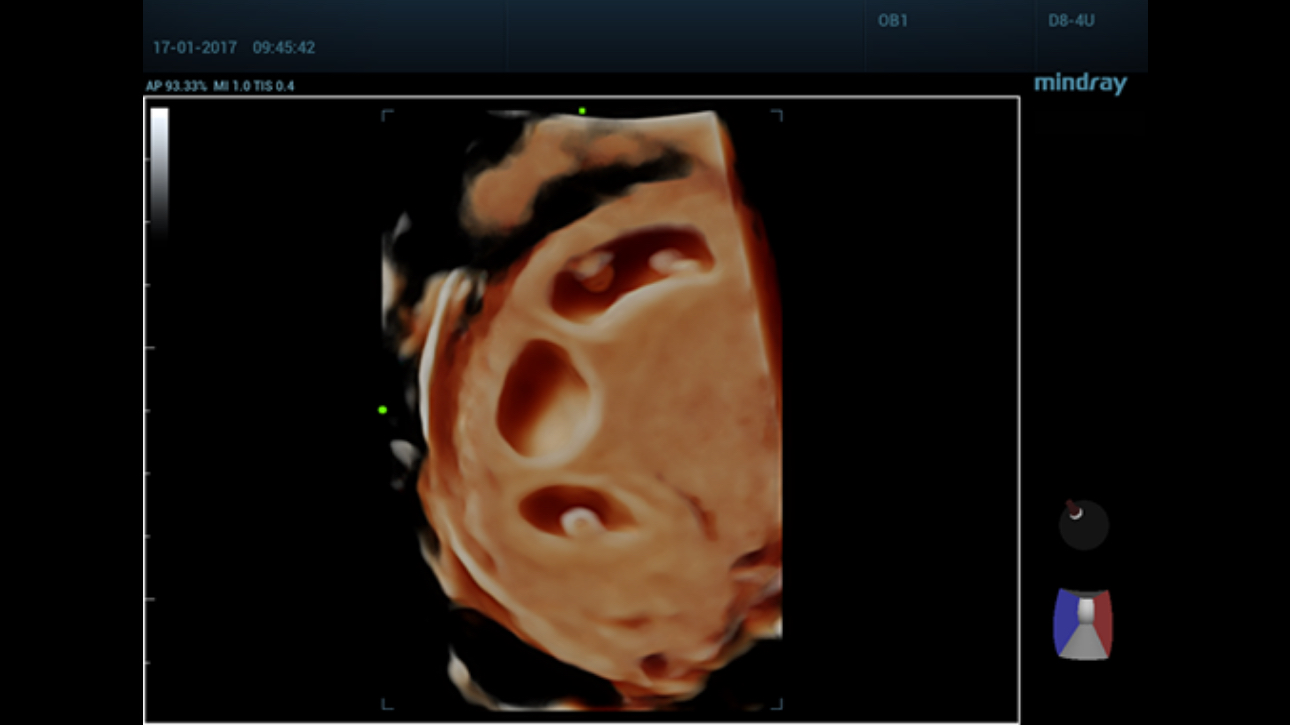

Comprehensive upgrading on iLive to significantly improve the detailed resolution as well as anatomical realism. Hyaline is a new rendering method that dynamically applies transparency to rendered structures for a more comprehensive view of anatomy, therefore better displaying internal anatomy from a solid surface.

The new Resona series with Zone Intelligence has further extended the capability of Smart Planes for intelligent fetal heart diagnosis. With extremely simple user-interaction of defining one point, it allows fully automatic and accurate detection of the six most important fetal cardiac planes. In addition, it helps standardize the orientation of the fetal heart images, and therefore improving the efficiency and effectiveness of fetal heart diagnosis.